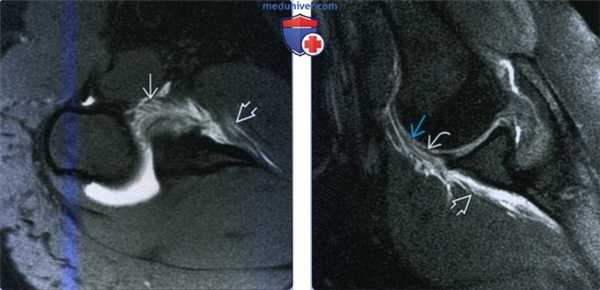

(Слева) Осевая МР-артрограмма Т1ВИ, пациент с разорванной нижней суставно-плечевой связкой после нижнего вывиха плеча. Передний пучок нижней суставно-плечевой связки разорван и разволокнен, а контраст вытекает в передние мягкие ткани.

(Справа) На артрограмме Т1ВИ FS с отведением и наружной ротацией у этого же пациента определяется разрыв переднего пучка нижней суставно-плечевой связки и вытекший контраст. Также визуализируется часть интактного переднего пучка нижней суставно-плечевой связки. Разрывы нижней суставно-плечевой связки после вывиха встречаются чаще у пожилых пациентов. Малые разрывы часто срастаются без операции.

(Справа) МР-артрография в режиме Т1ВИ FS, аксиальный срез: отмечается отслаивание переднего пучка НСПС от плечевой кости. Связка медиальнее разрыва утолщена. Передненижняя суставная губа интактна. (Слева) МР-артрография в режиме Т1ВИ FS, аксиальный срез: визуализируется отрыв заднего пучка НСПС, возникший после вывиха плеча. Наблюдается распространение контрастного препарата в мягкие ткани через дефект в заднем пучке НСПС.

(Справа) МР-артрография в режиме PD FS, сагиттальный срез, этот же пациент: прерывистый контур заднего пучка НСПС определяется лучше. Отмечается распространение контрастного препарата через дефект в капсуле сустава. (Слева) МР-артрография в режиме Т2ВИ FS, коронарный срез: визуализируется разрыв подмышечного кармана вследствие нижнего вывиха. Наблюдается распространение жидкости через дефект. Наличие жидкости латеральнее плечевой кости обусловлено отрывным переломом ее большого бугорка.

(Слева) МР-артрография в режиме PD FS, сагиттальный срез: визуализируется отрыв переднего пучка НСПС, возникший в ее средней трети. Наблюдается затек контрастного препарата в мягкие ткани книзу от сустава.

(Справа) МР-артрография в режиме Т1ВИ FS, коронарный срез, этот же пациент: отмечается распространение жидкости через дефекте нижней части суставной капсулы. По данным МРТ и артроскопии описанный дефект был изолированным. (Слева) МР-артрография в режиме Т1ВИ, коронарный срез: визуализируется утолщенная культя связки в форме буквы «J», что является не постоянным, но частым признаком отрыва переднего пучка НСПС.